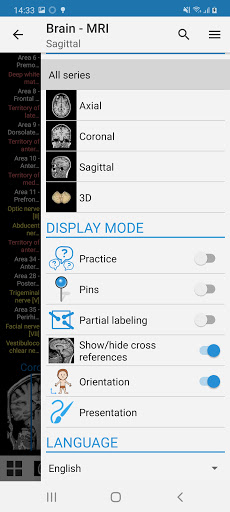

- Beberapa orientasi layar

- Ganti bahasa dengan satu sentuhan tombol